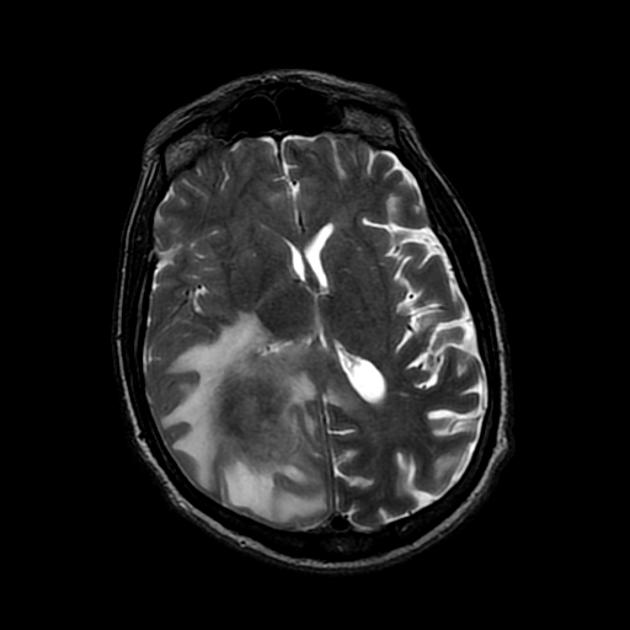

A detailed history and physical evaluation with particular attention to time course and nature of symptoms, followed by an MRI of the brain is the usual initial workup. The T1 MRI shows a hypointense or isointense lesion, and T2/FLAIR shows variable surrounding edema. T1/Gad shows homogenous enhancement without ring enhancement and lacking central necrosis. Ring enhancement occurs more often in immunocompromised patients.

MRI